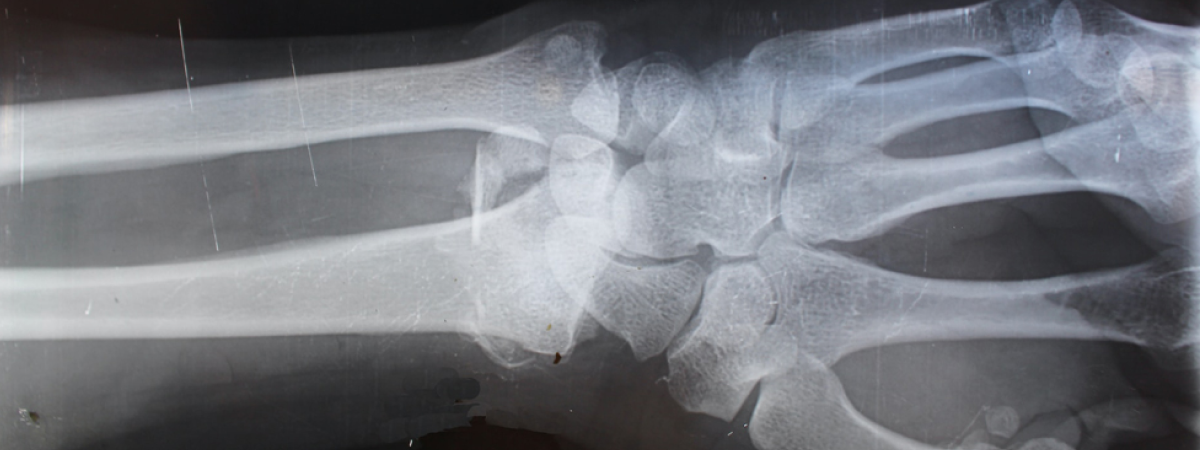

Las fracturas por fragilidad deberían ser prioritarias en los planes de salud

Este es uno de los aspectos destacados del Manifiesto para la prevención de las fracturas por fragilidad (FF) elaborado por la Plataforma para la Prevención de las Fracturas por Osteoporosis (PFO) con motivo del Día Mundial de la Osteoporosis, celebrado el pasado 20 de octubre. La plataforma es una iniciativa de la International Osteoporosis Foundation enmarcada en el programa internacional Capture the Fracture® que cuenta con la colaboración de UCB-Amgen.

En línea con la misión y la visión de la PFO, el documento traza diez líneas estratégicas para mejorar la prevención y el manejo de las FF en España, cuya incidencia es de 330.000 casos al año. Con el progresivo envejecimiento de la población, se estima que dicha cifra crecerá en la próxima década, hasta alcanzar las 370.000 FF al año.

Las FF conllevan una importante carga para los pacientes, tanto por la pérdida de autonomía como por la afectación emocional. De hecho, las fracturas osteoporóticas serían responsables de la pérdida de 12 años de vida ajustados por discapacidad por cada 1.000 personas de más de 50 años en España.